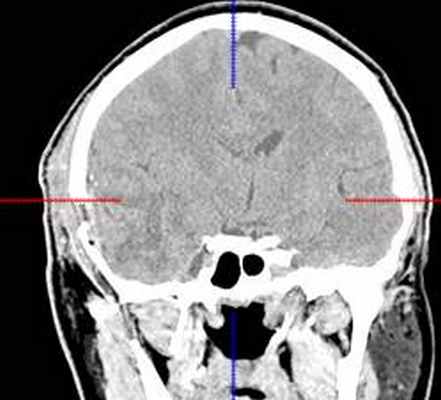

(б) МРТ, постконтрастное Т1-ВИ, аксиальный срез: у того же пациента контрастирования образования не определяется, что является типичным признаком ангиоцентрической глиомы. В смежной с опухолью области часто присутствует участок фокальной кортикальной дисплазии, который должен быть резецирован для предотвращения повторных судорожных приступов. (а) МРТ, Т1-ВИ, аксиальный срез: у шестилетнего ребенка с рефрактерной эпилепсией в структуре коры и субкортикального белого вещества определяется слабовыраженное образование. Обратите внимание на гиперинтенсивные кольцевидные участкичто типично для ангиоцентрической глиомы.

(б) МРТ, Т2-ВИ, корональный срез: у того же пациента определяется повышение интенсивности сигнала от образования, расположенного в области коры и субкортикального белого вещества правой лобной доли. При хирургической резекции была диагностирована ангиоцентрическая глиома. Визуализационные признаки могут напоминать признаки чаще встречающейся ДНЭО.